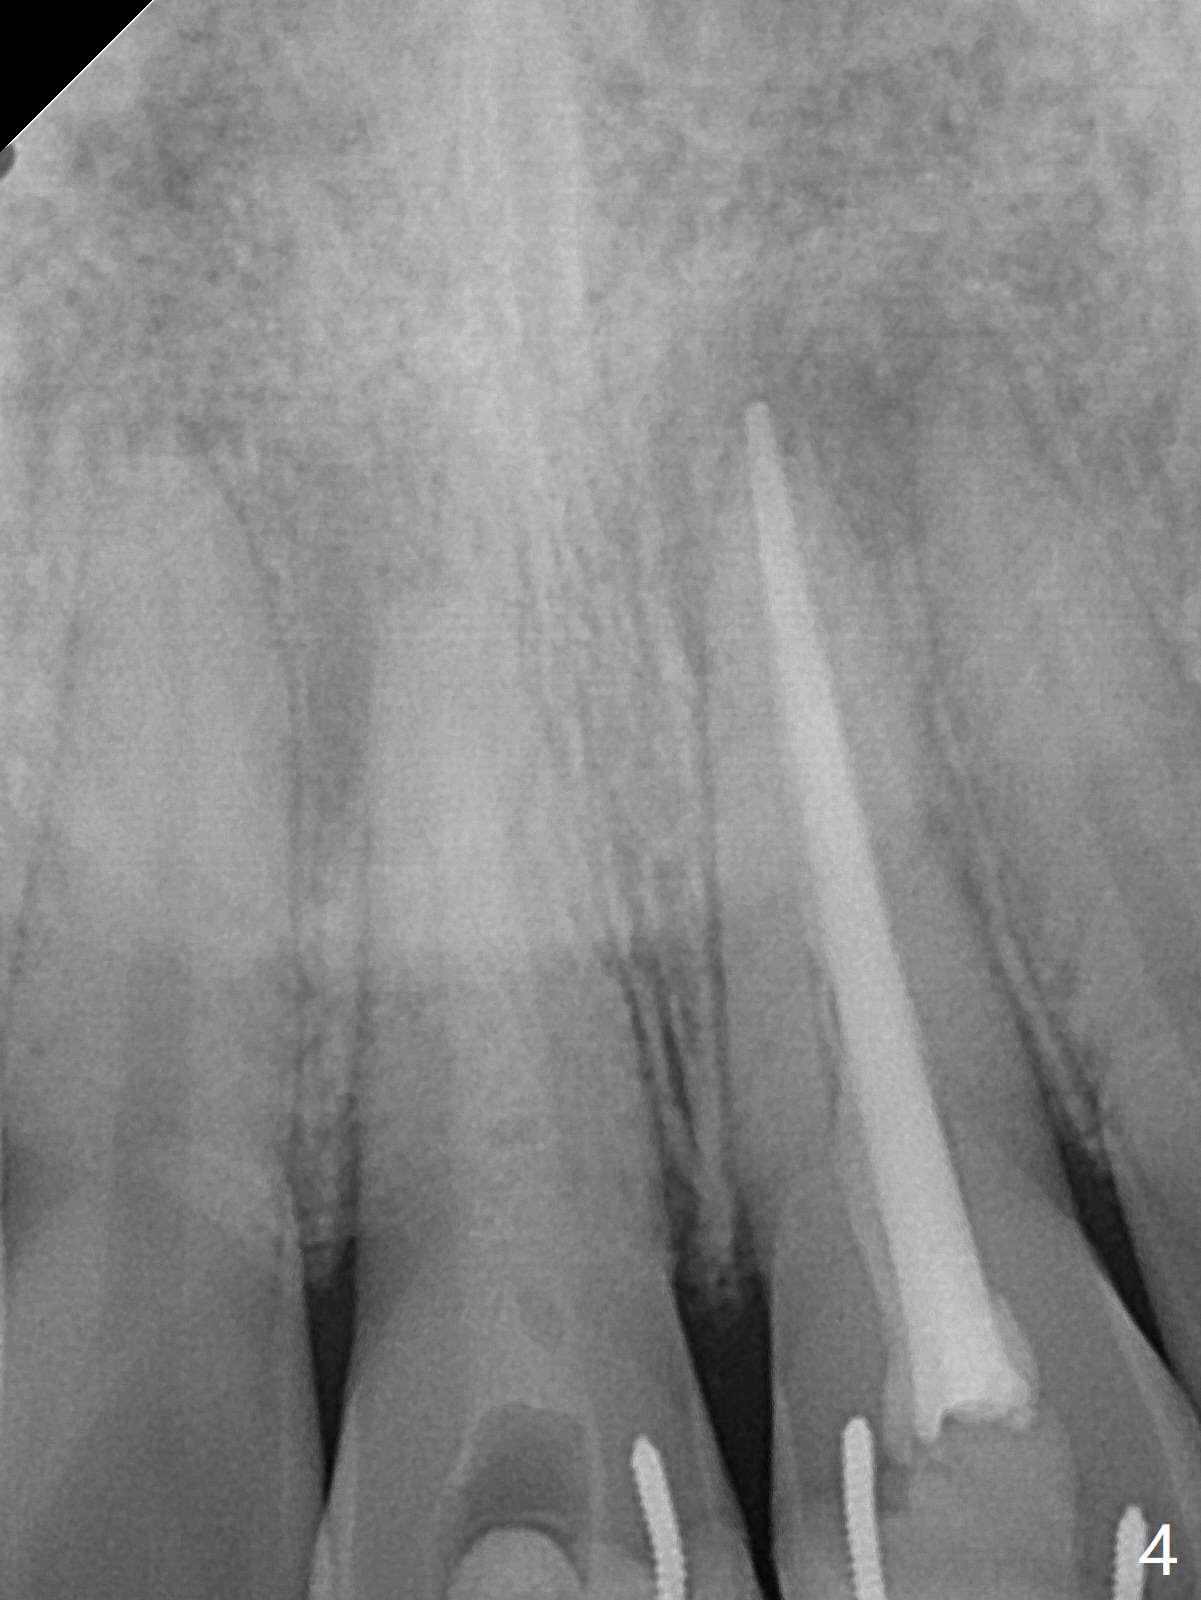

15岁男去年急诊来诊所左上1疼痛(图一:9号牙),两个中切牙8-9岁外伤,侧切牙活性测定:活髓,建议8,9 apexification。一年后(这个月)他又回来要求9号牙树脂修复(图二:*),他在马来西亚看望爸爸时,突然牙痛在那里做根管治疗。现在两个中切牙颊侧根尖都有触痛。树脂修补后,他回来做8号牙牙髓治疗,想象根管宽大,但是根尖2-3毫米根管弯曲,必须事先弯曲10号扩大针才能进入,最后扩大针是rotary file, 40/.04, 21.5毫米(图三),好像工作长度不够,仅仅增加半个毫米,使用15号扩大针,病人觉得疼痛(没用局麻药),不再扩大,保持原来根尖狭窄(可以吗?)。反复冲洗后放置氢氧化钙糊剂(图四),根管仿佛挺粗的,根尖根管还需要扩大吗?根尖片清晰度不好,看不出根尖闭锁与否,需要拍摄CT吗?需要使用MTA促进根尖关闭吗?